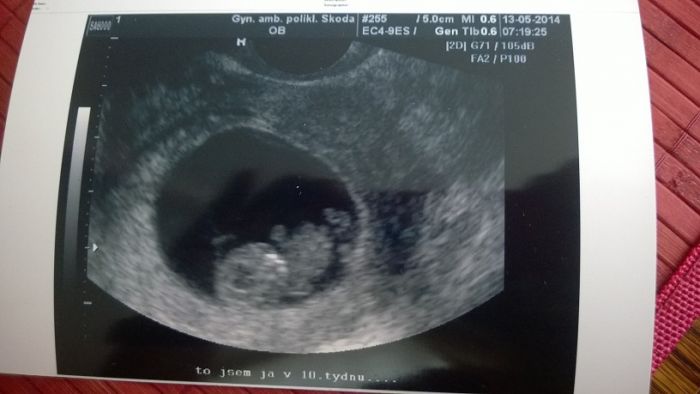

Začínáme 12.týden, TP určen na 14.12., podle ultrazvuku, podle MS se určit nedá :-)), protože nebyla...

Tady fotečka našeho zlatíčka... a konečně i průkazka....jupííí, screening nás teprve čeká,...tak ťuk ťuk...